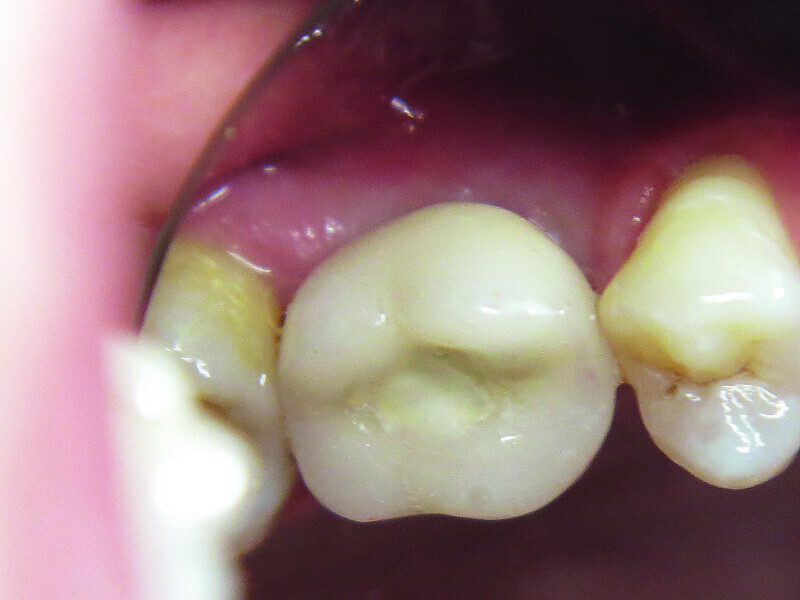

Fig. 7: Situation after treatment.